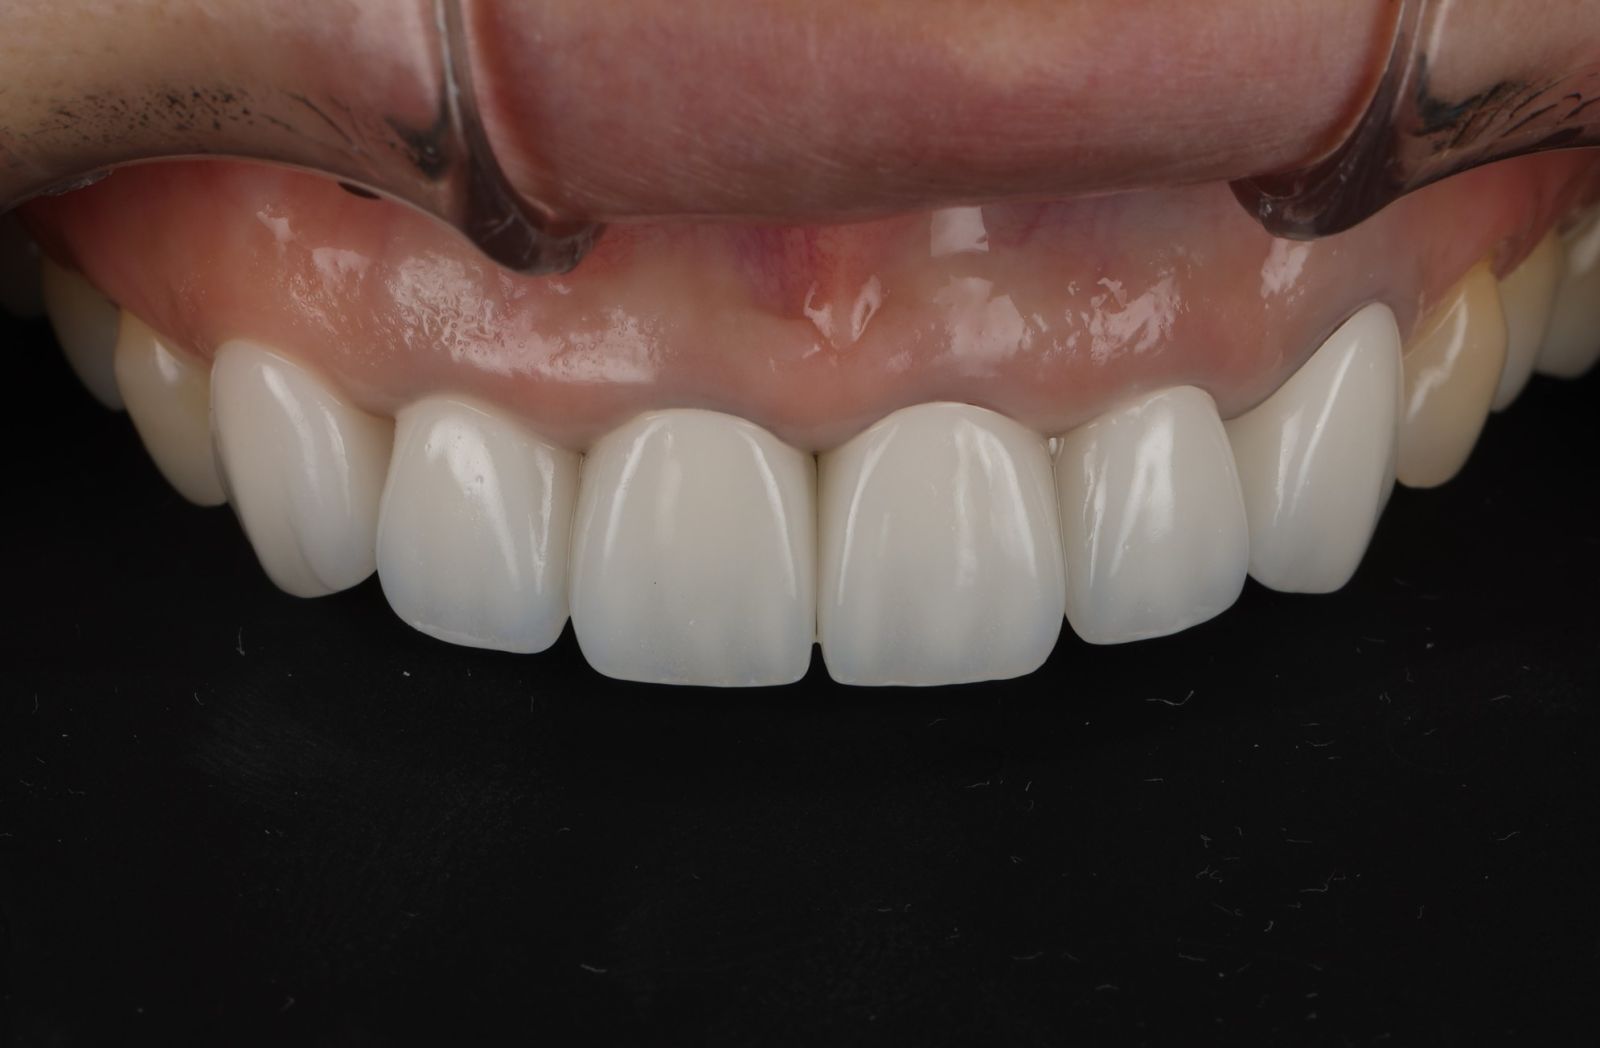

- 先把舊的假牙拆除後換成臨時假牙,期間先做冷光美白讓牙齒的基礎顏色變白,用保養型冷光美白,讓其他自然牙的部分可以白2~3個色階。一段時間讓顏色穩定後就可以當作正式全瓷冠的顏色參考。

-

經過數位微笑曲線設計,選擇自己喜歡的色階後就可以製作適合自己的美學全瓷牙囉!全瓷冠經過特殊處理呈現的通透感,讓牙齒白而自然透亮。